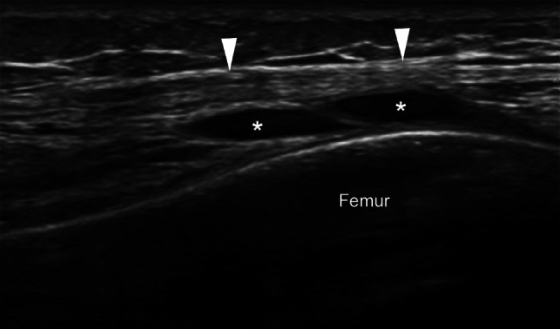

髂胫束综合征或摩擦综合征是膝关节外侧过度使用的疾病。它在运动员(例如跑步和自行车)群体中高发。超声影像作为一种高性价比的成像方式,能够以高分辨率、动态评估以及与对侧健康侧进行比较来显示浅表软组织结构,对于评估髂胫束综合征具有重要参考价值。

- 关于第一点的“摩擦说”:与髂胫束在涉及重复膝关节屈伸的活动中来回摩擦股骨外上髁有关,从而导致髂胫束摩擦和邻近软组织发炎。多年来,这一病因一直存在争议,特别是关于髂胫束运动的方向和程度。然而,一项超声研究表明,在膝关节伸展和屈曲期间,髂胫束相对于股骨外上髁沿前后方向移动,因此支持摩擦作为病因学因素的核心作用。